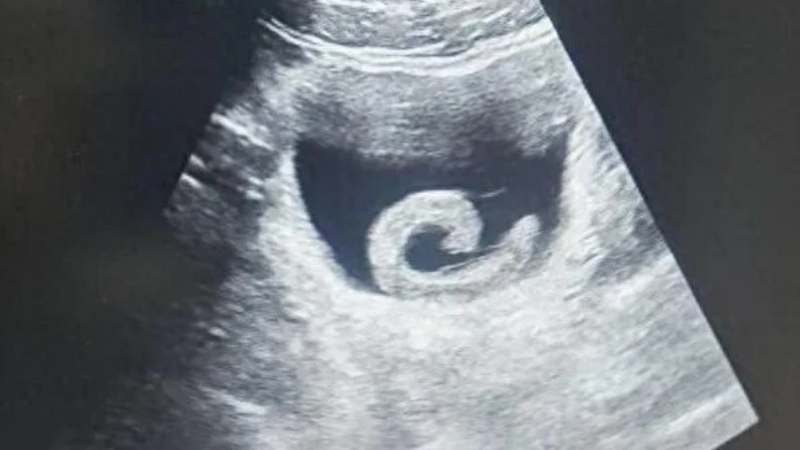

CONTINUA DEPOIS DA PUBLICIDADEInicialmente incrédulos, os médicos solicitaram exames de imagem. Um ultrassom confirmou a presença do parasita vivo dentro da bexiga. Diante do risco à saúde do paciente, a equipe médica preparou uma cirurgia imediata para a remoção do corpo estranho.